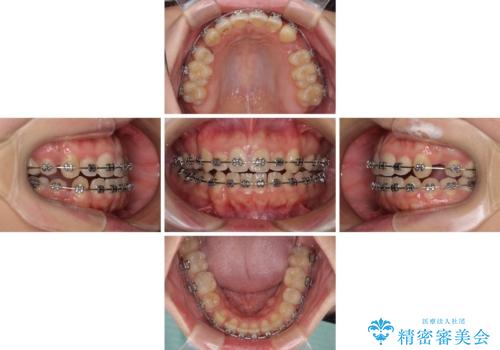

- 矯正装置

- メタルブラケット

- 1年7ヶ月

- 治療回数

- 10-30回